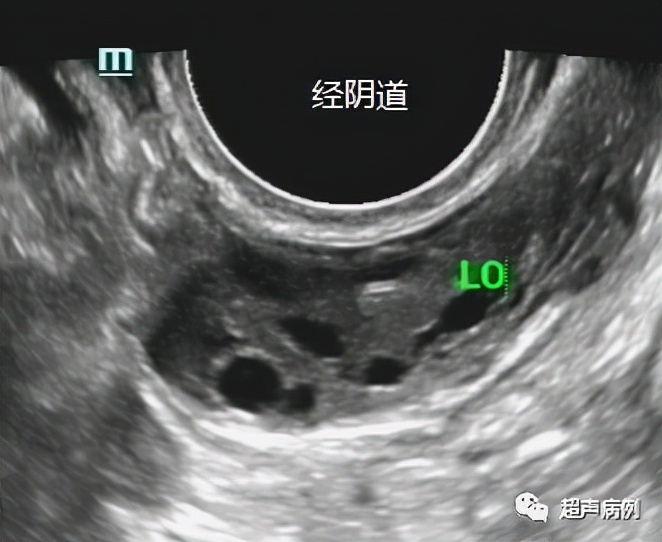

下图就是分别经腹部及经阴道超声的检查对比图。

可以看出经腹部的超声不能看清较小的卵泡及卵巢的细微结构,而经阴道超声就能看得清清楚楚。